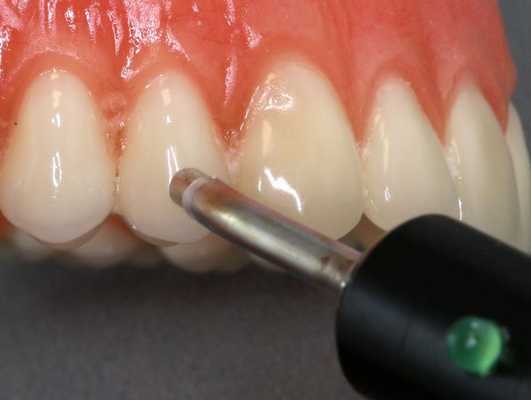

ЭОМ — это метод стоматологического исследования, основанный на определении порогового возбуждения болевых и тактильных рецепторов пульпы зуба при прохождении через неё электрического тока.